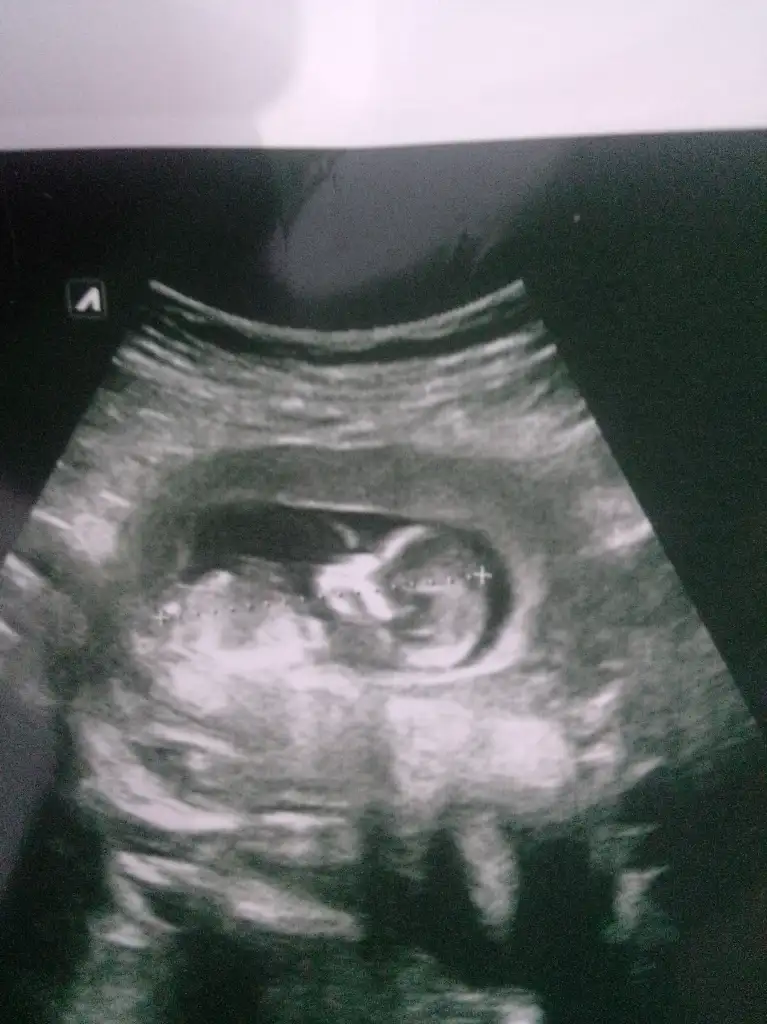

Tam 12. Haftadayız. Bugün doktor erkek gibi dedi ama kesin konuşmadı. Açıkçası ben de kafasını ense yapısını çene yapısını erkeğe benzetiyorum. Bir de nub a göre duruşuna göre erkek gibi dedi ama soru işareti ile.

Kesin erkek diyeceğim bi bakıyorum görüntüye 3 çizgi var bacaklarının o tarafta.Kızlarda 3 çizgi oluyormuş , o yüzden erkek mi emin olamıyorum kafam karışıyor anlayan biri varsa bakabilir mi